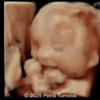

A 33-year-old nullipara with non-contributory medical history presented at 20 weeks, 6 days based on an early scan. Ultrasound revealed the following findings. There were no other apparent abnormalities. What is the most probable diagnosis?